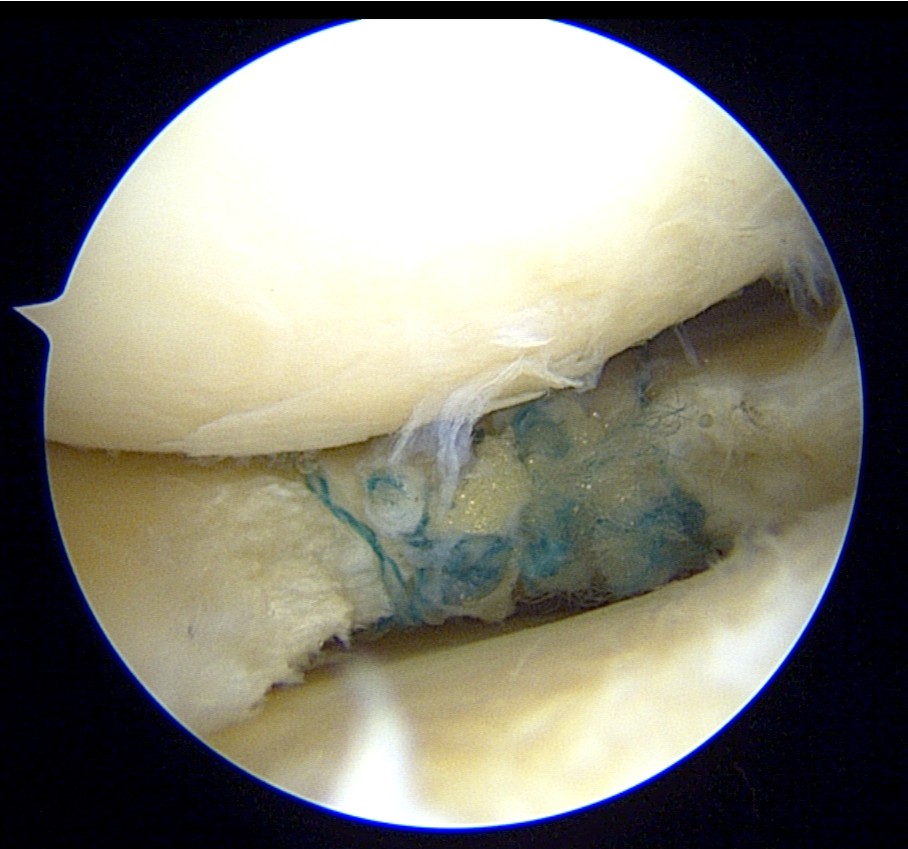

The tear was then repaired using the Smith & Nephew’s NOVOSTITCH.

The cyst material was decompressed as much as possible through the tear.